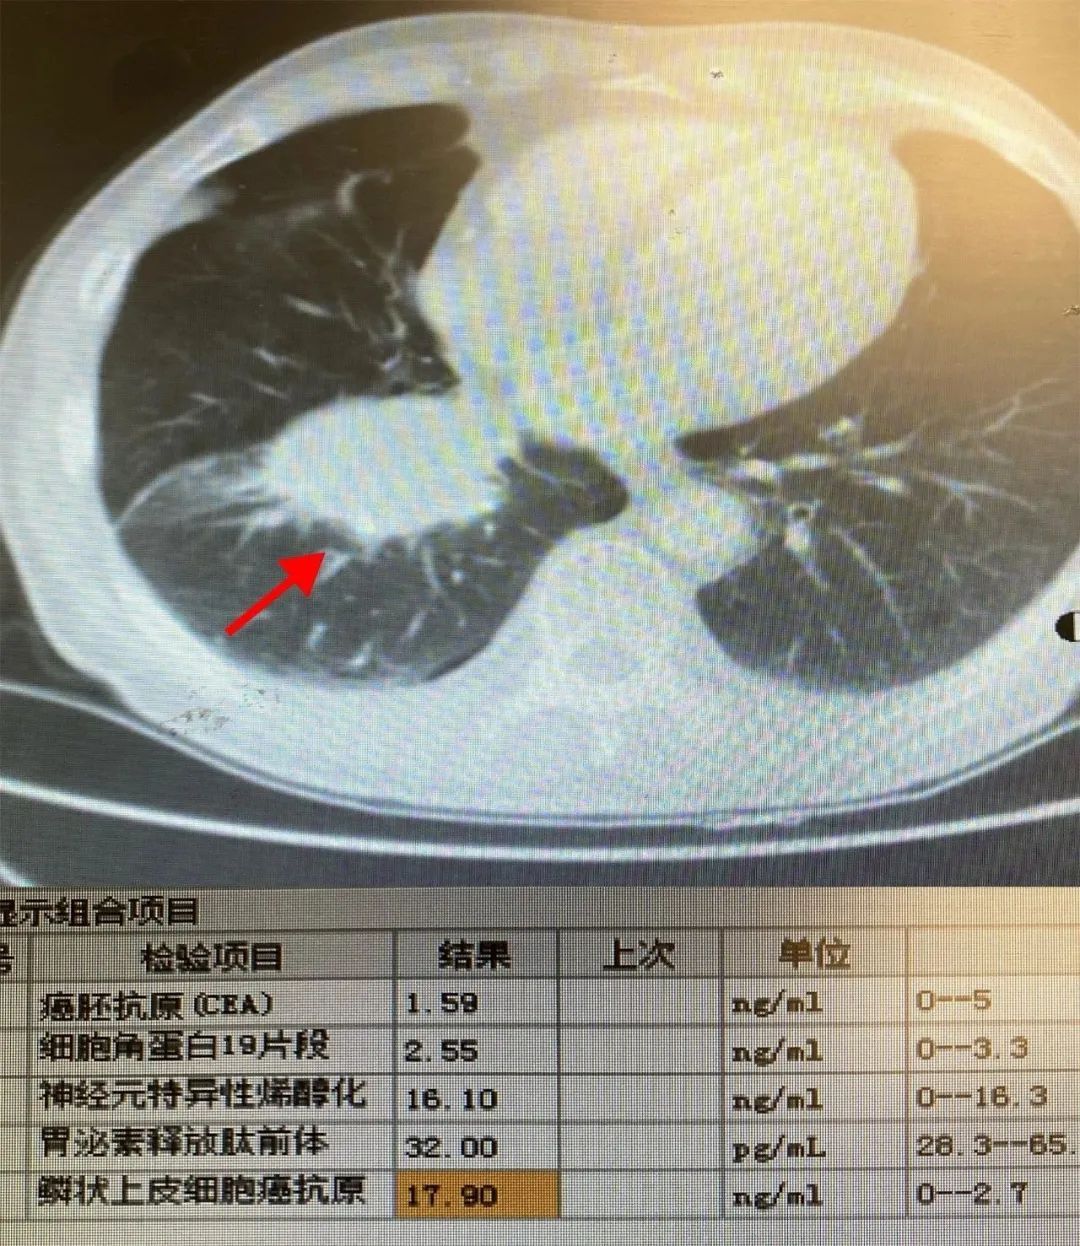

2023-03-02医路前行,“醉”美守护——一例高危全麻支气管镜检术

“什么?患者PCI(经皮冠状动脉介入治疗)术后2个月?” 麻醉科姜继述主治医师在电话里说道,“好的,我马上到!” 近日,市九院呼吸与危重症医学科联合手术麻醉科、... -